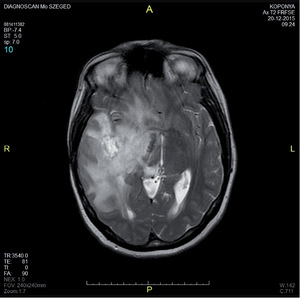

3.6.2. Daganatok: az agy (64–72. ábra)

- MRI: T2, FLAIR, T1/T1gad, DWI.

- CT: natív és kontrasztos – akut eset, staging, mész kimutatására.